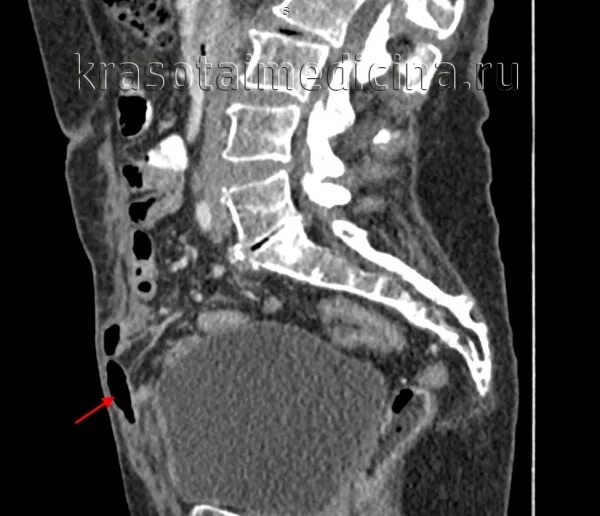

Грыжи на кт